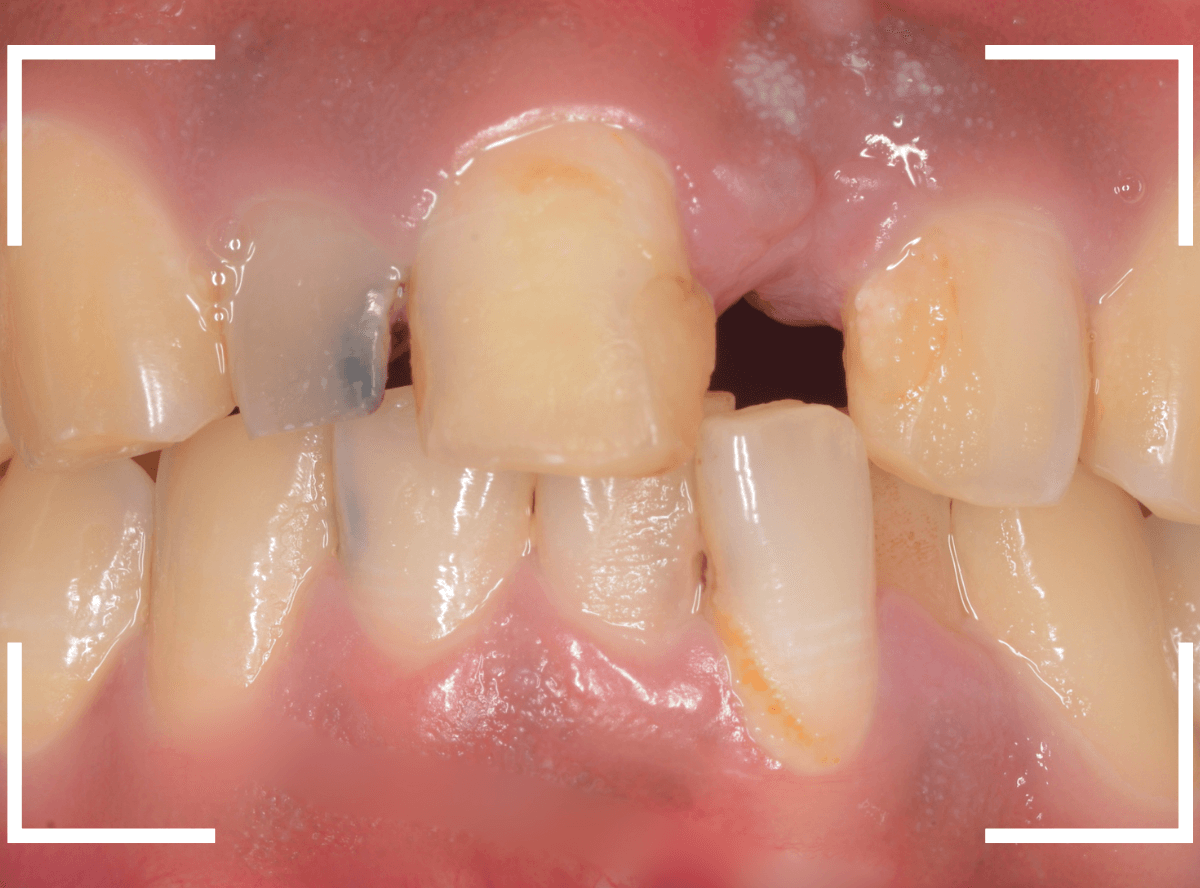

今回は、前歯につめたレジンが、毎回、すぐに欠けてしまうので直してほしいと来院された患者さんのケースです。

お口を閉じてもらうと、下のがレジンをつめたを突き上げて当たってしまうようです。

これでは、すぐに外れてしまっても仕方ありません。

治療を変える必要がありそうです。

レントゲン写真上では、歯は問題なさそうでしたが、隣の歯に比べてやけに変色しているので「怪しい」と、歯の神経を調べてみると、神経が死んでいました。

下の歯が常に突き上げている刺激が原因で、死んでしまったのかもしれません。

また、歯の周りの歯石も多く、歯周病も進行気味でしたので、

- 歯の神経の治療

- 歯周病の治療

- さし歯(クラウン)の治療

- 下の歯を含めた嚙み合わせの調整

といった治療が必要で、最終修復まで期間がかかる事をご説明の上、同意されました。

まず、歯周病の治療と並行して、神経の治療を行います。

さし歯を被せるために、歯の土台をたてて、歯を削ります。

歯の高さが低く、このままさし歯を作っても、すぐに取れてしまう事が予想されます。

隣りの歯と比べても歯肉の際が浅いため、若干歯肉を切開して、歯の高さを稼ぎます。

歯肉を切開した部分に、仮歯のレジンを盛って確認します。

大体、隣の歯の高さと合わせる事が出来ました。